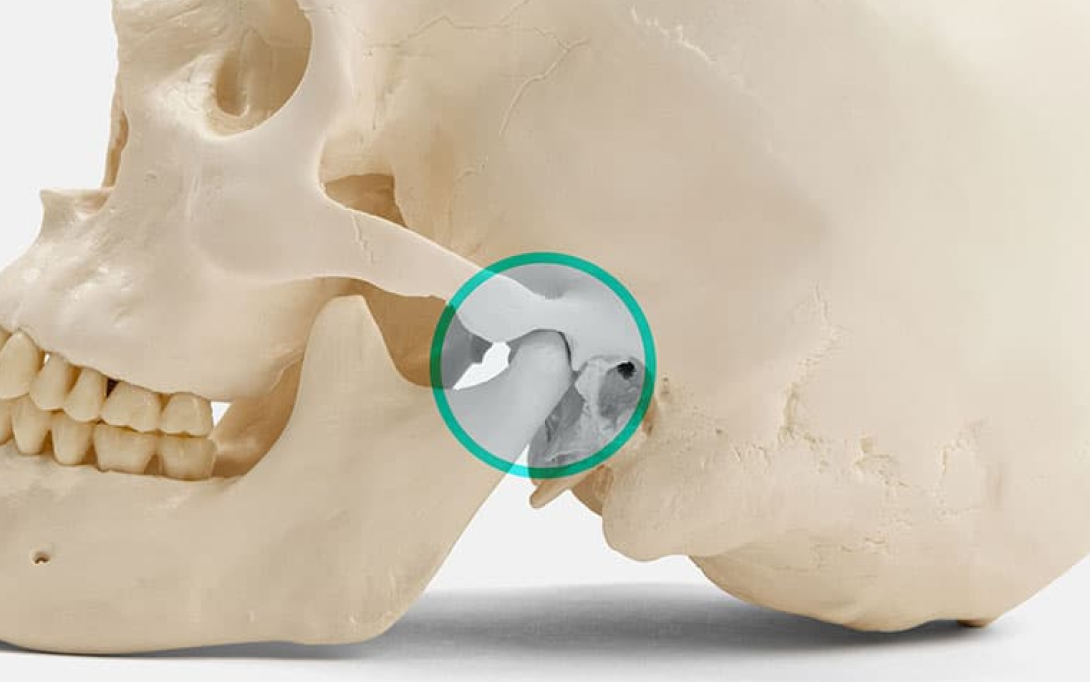

Media Text – C (With Hotspot)

Lorem ipsum dolor sit amet, consectetur adipiscing elit. Mauris eu nunc nec velit efficitur consequat. Quisque volutpat mattis ante, id viverra ligula molestie eget. Pellentesque velit orci, convallis eget sapien ut, viverra varius neque. Nunc sed lacus vitae purus gravida ornare. Ut volutpat enim magna, vel finibus magna ultricies eget. Cras cursus laoreet risus, feugiat congue lacus semper eu.